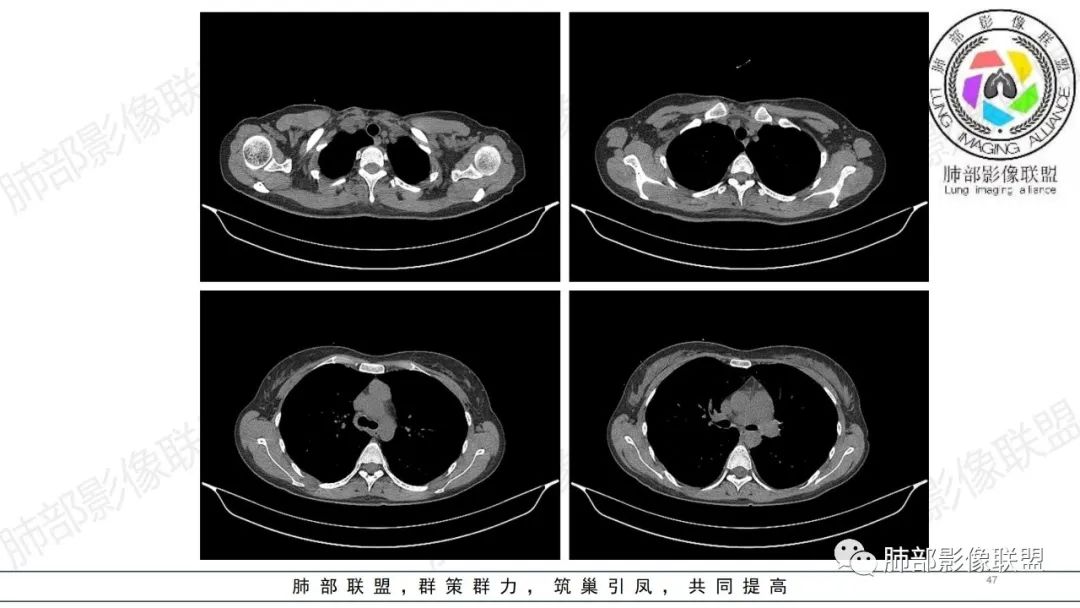

血管内大B

同意血管大B

跟弥漫大B

跟淋巴瘤

肺内气腔磨玻璃结节,肝脾肿大,治疗后间质改变,弥漫大B可能